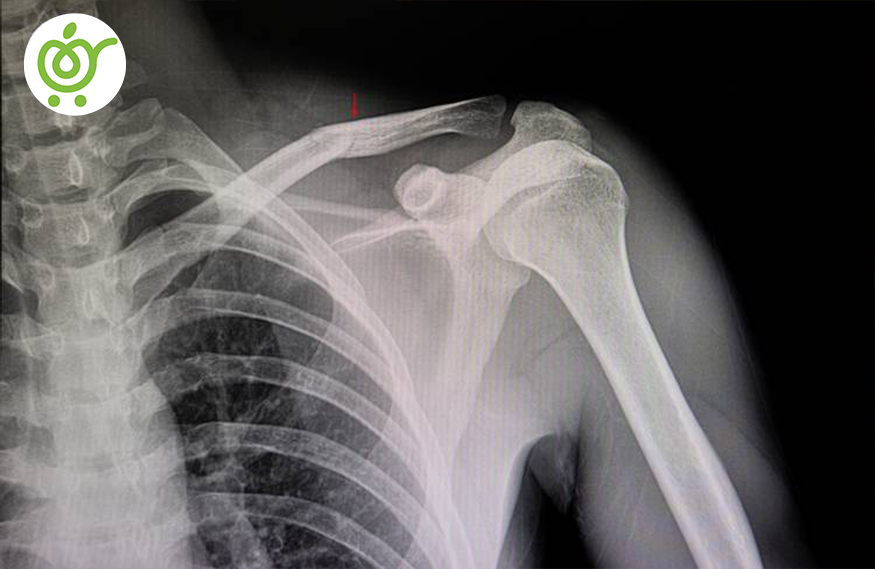

در رفتگی

در رفتگی زمانی رخ میدهد که قسمت انتهایی استخوان از جایگاه خود خارج شود. عواملی که موجب این معضل میشود شامل تصادف و وزرش و تحرکات بدنی که دارای سرعت بالایی دارد. در بزرگسالان اکثراً شانه دچار این مشکل میشوند و در کودکان بیشتر در قسمت آرنج آنها این مشکل پدیدار میشود.

در رفتگی بیشتر در استخوانهای بزرگ دیده میشود. در صورت مواجه شدن با این مشکل، سریعاً به یک دکتر ارتوپد مراجعه نمایید.

- دررفتگی مفصل شانه